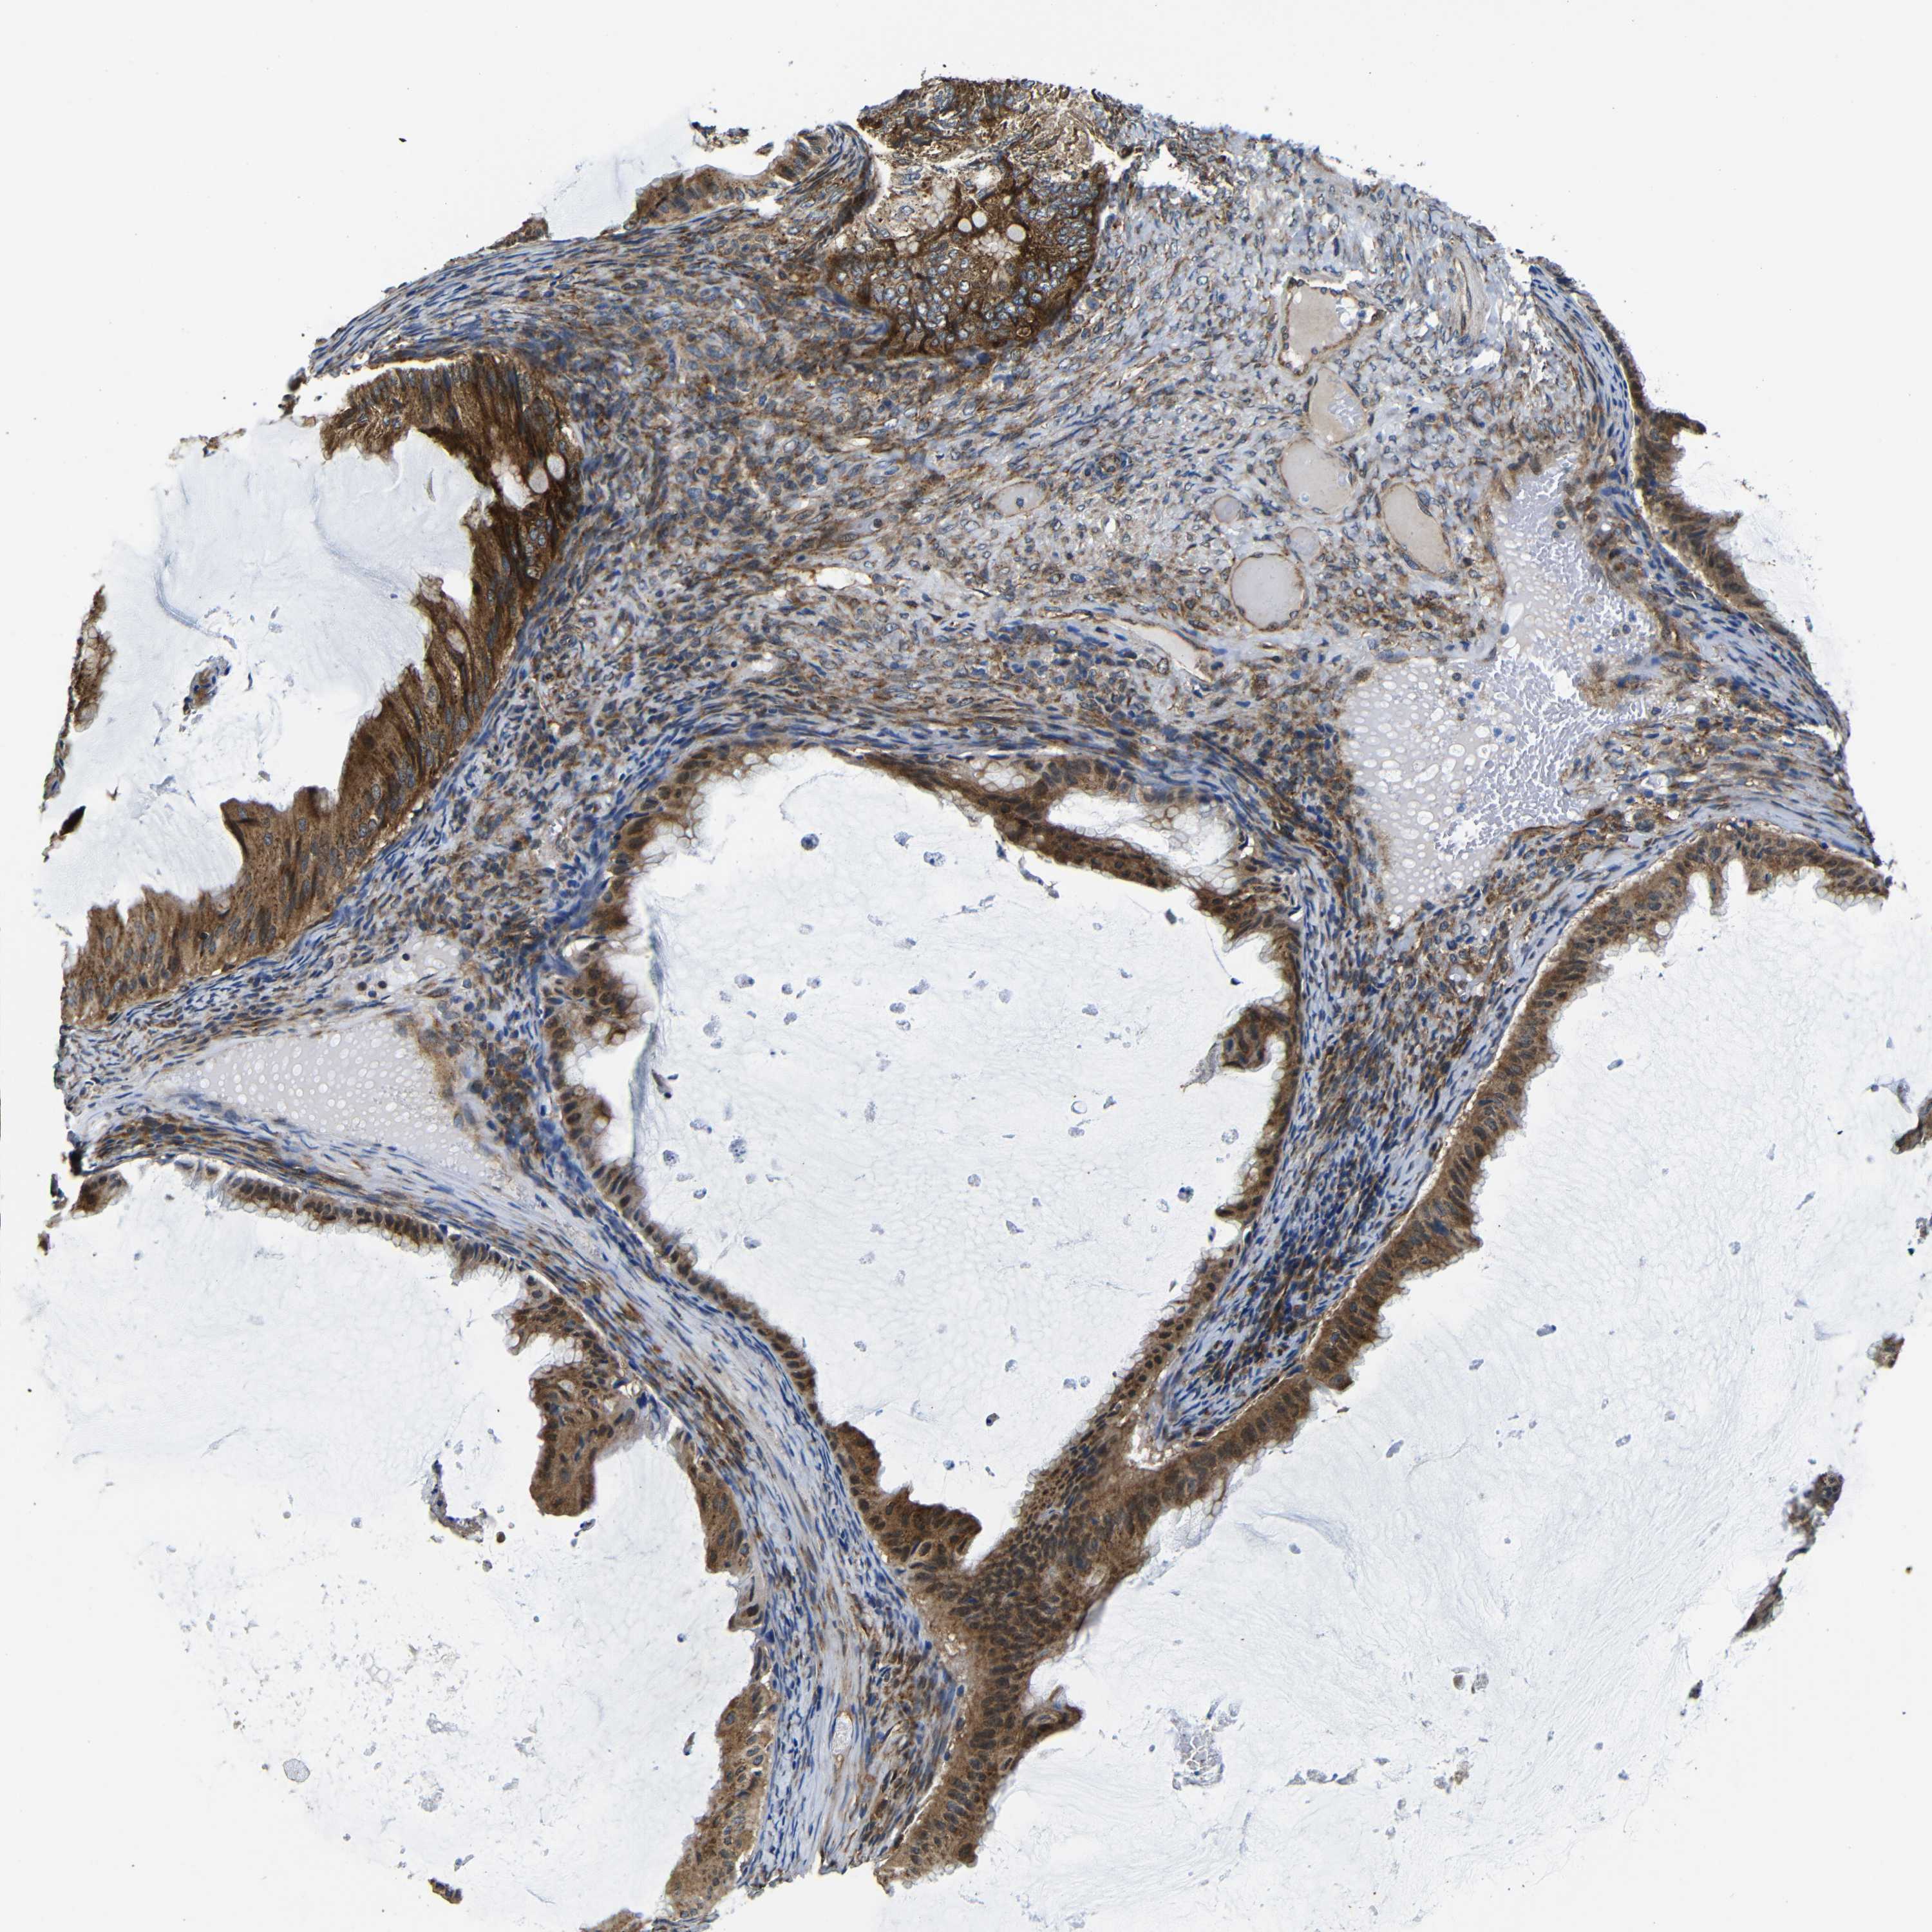

OVARIAN CANCER - Protein expressioni

A mouse-over function shows sample information and annotation data. Click on an image to view it in a full screen mode. Samples can be filtered based on level of antibody staining by selecting one or several of the following categories: high, medium, low and not detected. The assay and annotation is described here.

Note that samples used for immunohistochemistry by the Human Protein Atlas do not correspond to samples in the TCGA dataset.

Antibody stainingi

Antibody staining in the annotated cell types in the current human tissue is reported as not detected, low, medium, or high, based on conventional immunohistochemistry profiling in selected tissues. This score is based on the combination of the staining intensity and fraction of stained cells.

Each image is clickable and will lead to virtual microscopy that enables deeper exploration of all samples and also displays staining intensity scores, fraction scores and subcellular localization as well as patient and tissue information for each sample.

Antibody CAB012476

Cystadenocarcinoma, serous, NOS

Carcinoma, endometroid

Cystadenocarcinoma, mucinous, NOS

Carcinoma, NOS